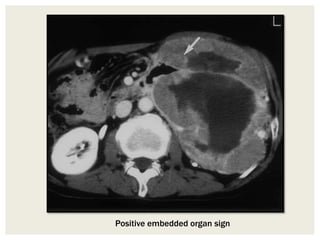

Embedded Organ Sign

When a tumor compresses an adjacent

plastic organ (eg, gastrointestinal tract,

inferior vena cava) that is not the organ of

origin, the organ is deformed into a crescent

shape.

When part of an organ appears to be

embedded in the tumor (positive embedded

organ sign), the tumor is in close contact

with the organ and the contact surface is

typically sclerotic, and ulcerative with

desmoplastic reaction. And it is likely that

the tumor originates from the involved

organ.

Positive embedded organ sign